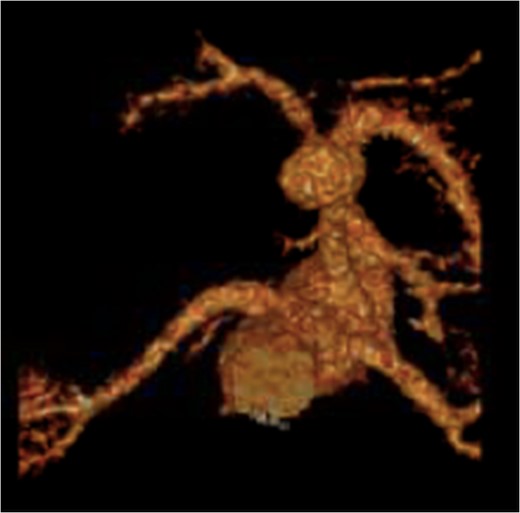

CT abdomen with contrast demonstrating the location and size of the aneurysm.

Recreated 3D imaging of the aneurysm arising from the ventral aspect of the distal celiac artery.